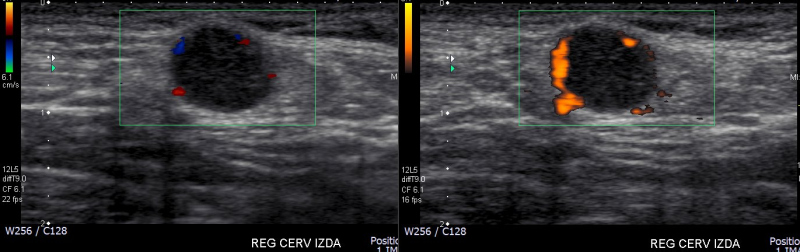

Mujer de 57 años, que consulta en diciembre de 2014 por aumento de volumen cervical izquierdo, asintomático, de 2 años de evolución. Dos ecografías cervicales de agosto y noviembre del 2012 describen adenopatía hiperecogénica, con cápsula vascularizada al Doppler color. En ecografíareciente se destaca nódulo subcutáneo de 10 mm en hombro izquierdo, bien delimitado, rodeado por una cápsula vascularizada, hipoecogénica de forma heterogénea (Figs. 1a y b). Se realiza estudio histológico mediante punción aspirativa con aguja fina de la adenopatía, la cual resulta negativa para células neoplásicas. Posteriormente se realiza biopsia incisional del nódulo subcutáneo mostrando infiltración del tejido conectivo por neoplasia que tiene caracteres morfológicos e inmunohistoquímicossugerentesde HEE con necrosis tumoral parcial.